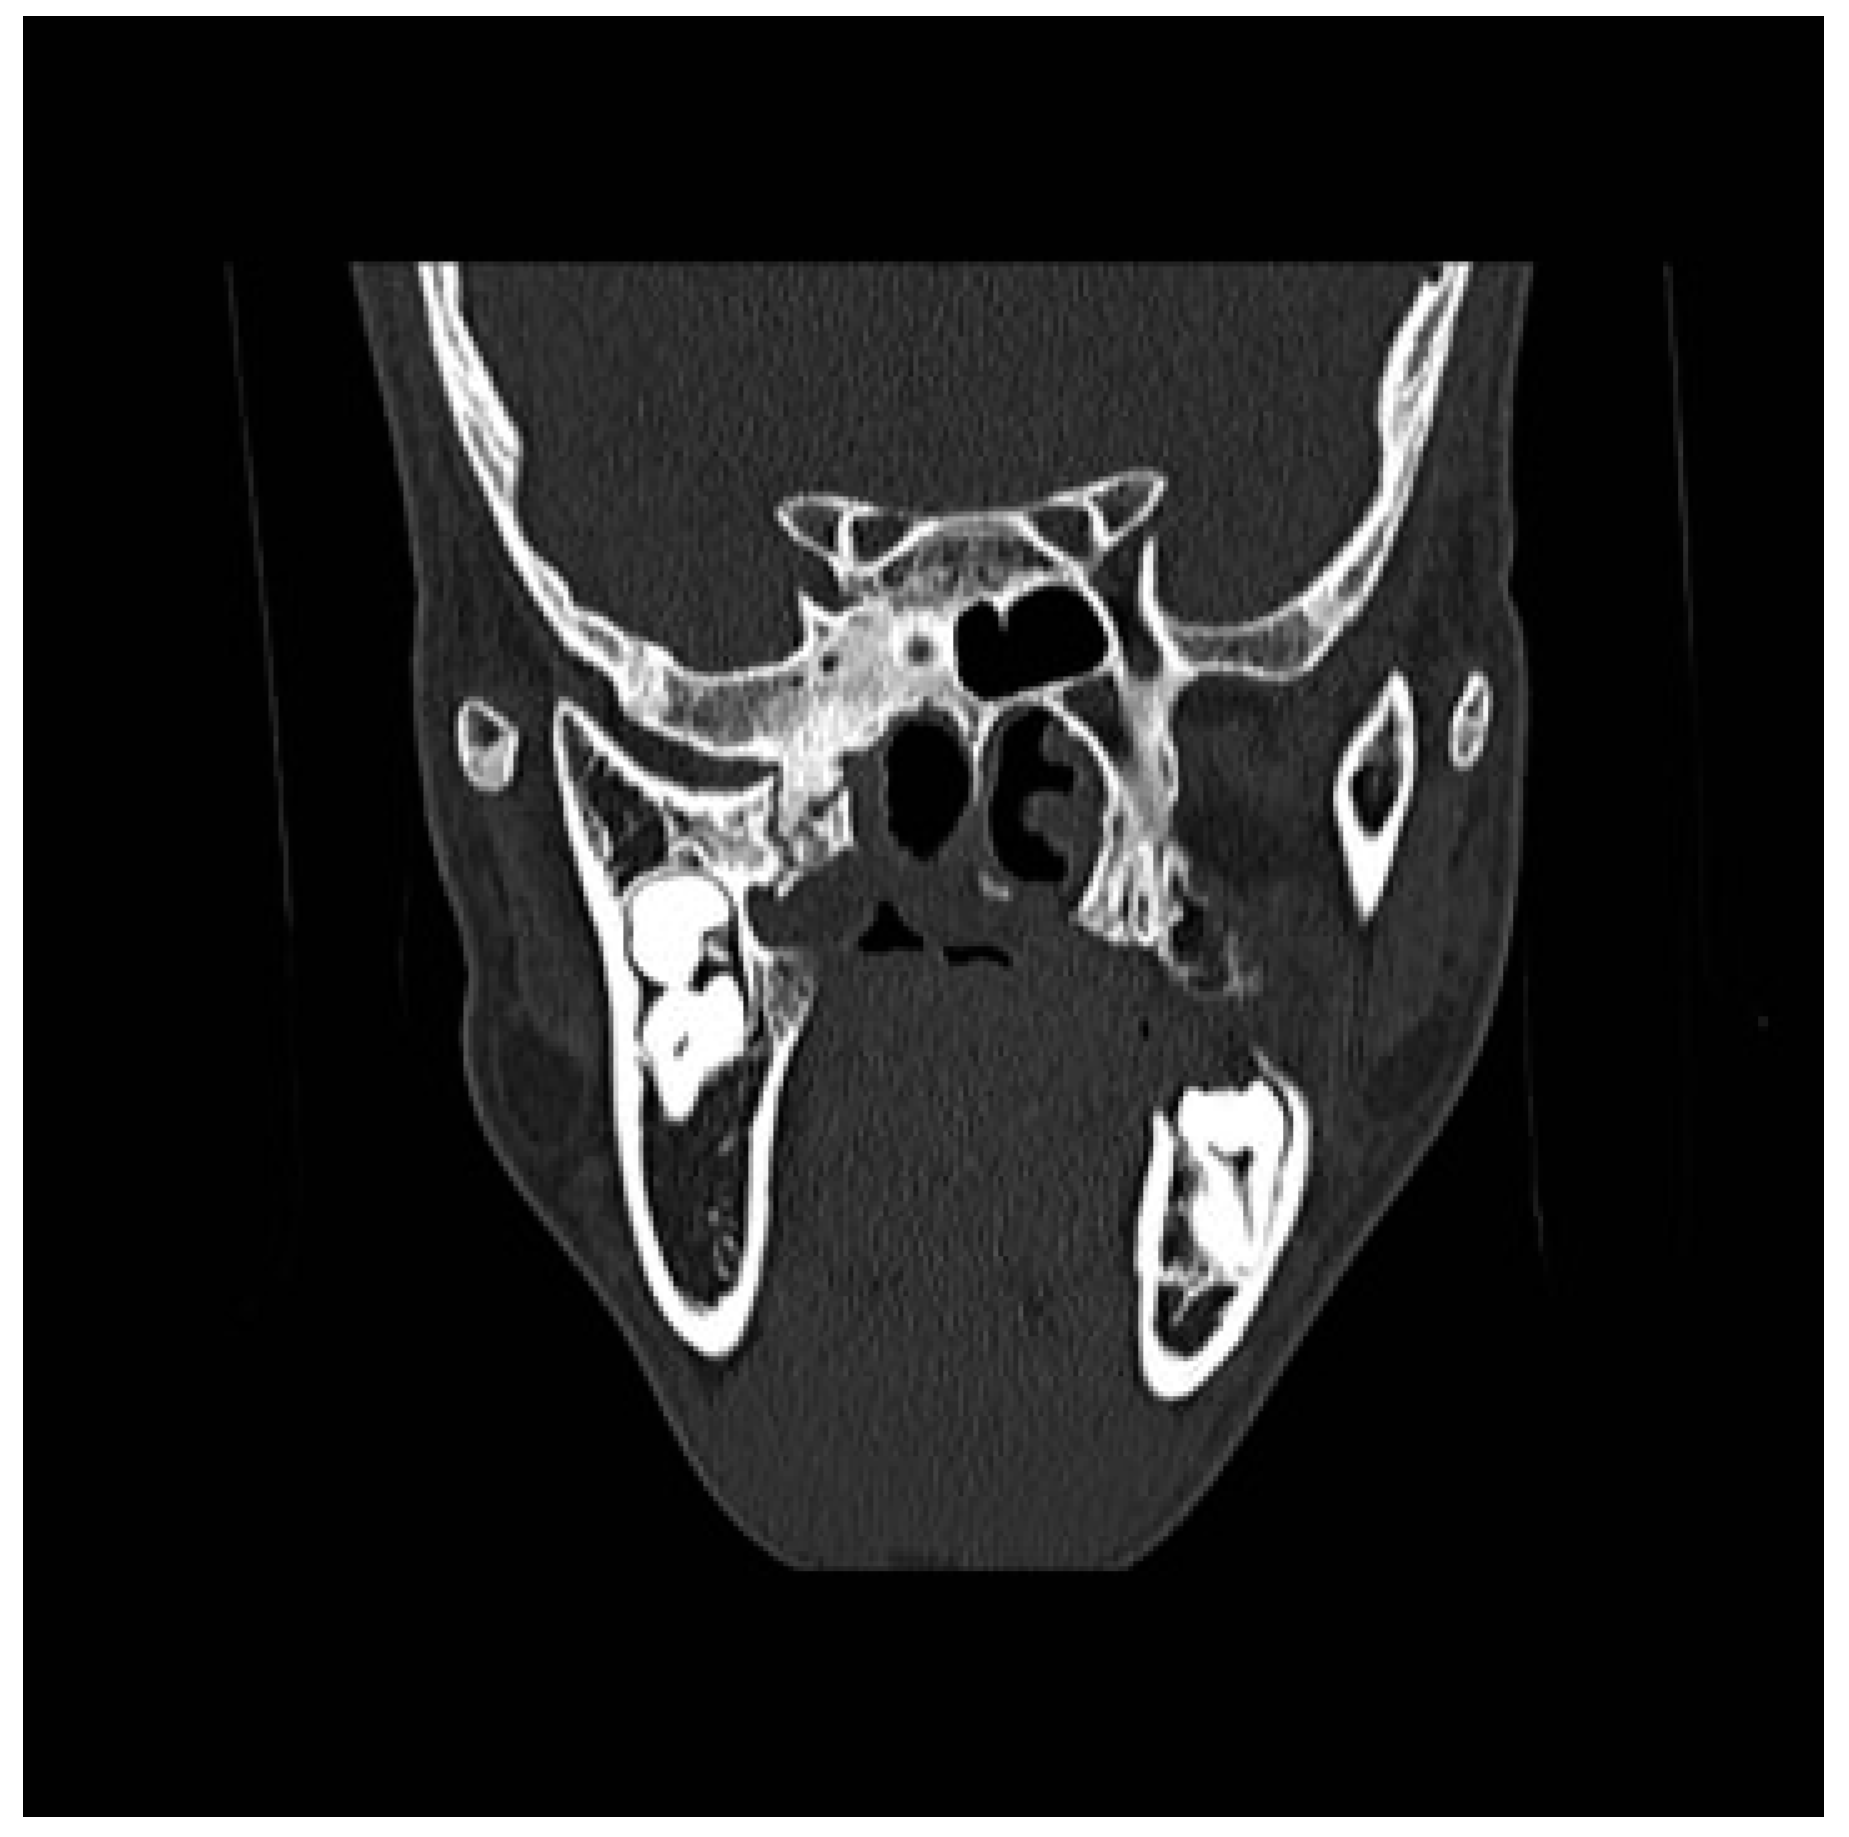

Figure 3. Preoperative CT scan. Coronal view: right maxillomandibular fusion.

A CT scan of the head with 3D reconstruction (Figure 1, Figure 2, Figure 3, Figure 4 and Figure 5) confirmed a maxillomandibular fusion associated with a cleft palate, agenesis of the right turbinate, and right hemifacial microsomia (Laster type 2b syngnathia). Both temporomandibular joints (TMJs) were normal and showed no bony ankylosis (fibrous ankylosis could not be excluded with the given data).